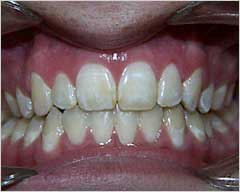

هي حاله بسيطه قبل وبعد للتقدم بسيط او بروز في الفك العلوي